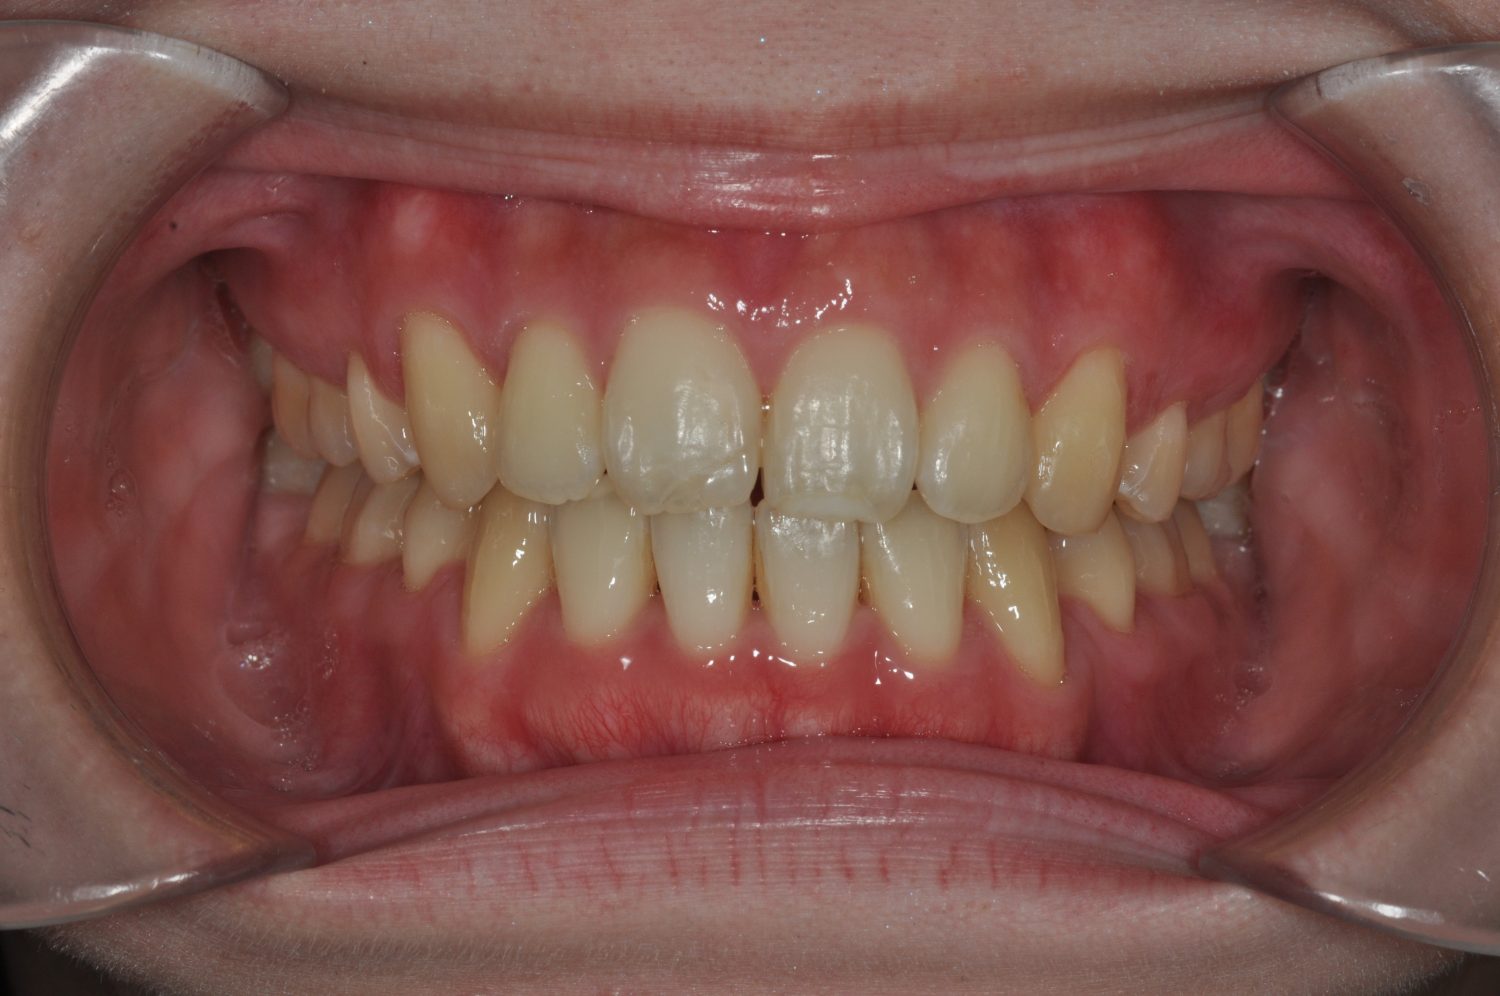

| 主訴 | 前歯部の叢生と正中の不一致 |

| 治療内容 | 軽度の叢生の改善を行うために、非抜歯でのマルチブラケット装置による治療を行った。 |

| 治療費 | Ⅱ期治療費:275,000円(税込) 調整料 5,500円(税込)×18回 保定時:22,000円(税込) 計 396,000円(税込) |

| 治療期間 | 2年2ヶ月 |

| 治療回数 | 20回 |

| 想定されたリスク | 矯正後に後戻りする可能性がありました。 |

Ⅰ期治療で叢生、反対咬合の改善をセクショナルアーチとMPAを使用して改善した後、成長観察を行っていました。永久歯の萌出したため、Ⅱ期治療を開始することとなった。上下顎とも骨格的に問題がなかったため、非抜歯で治療を行った。